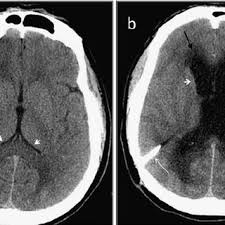

Radiological Findings Before And After Vp Shunt Placement Notes A Download Scientific Diagram